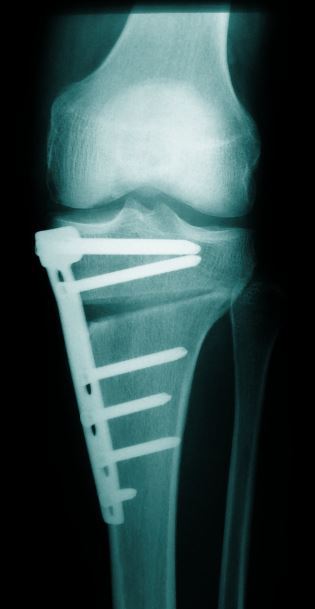

Umstellungsosteotomien

Besteht zusätzlich zum Knorpelschaden auch eine Achsfehlstellung des Kniegelenkes (z.B. O-Bein), kann eine Umstellungsosteotomie erfolgen.

Hierdurch soll die Beinachse so verändert werden, dass die Belastung mehr in den Gelenkbereich mit dem gesunden Knorpel verlagert wird.

So kann meist der Zeitpunkt bis zum Einsetzen eines künstlichen Kniegelenkes hinausgezögert werden.